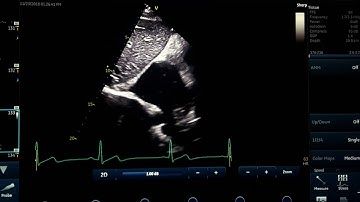

Bicaval view echo for beginners l Subcostal view l for sinus venous ASD #echo #shorts